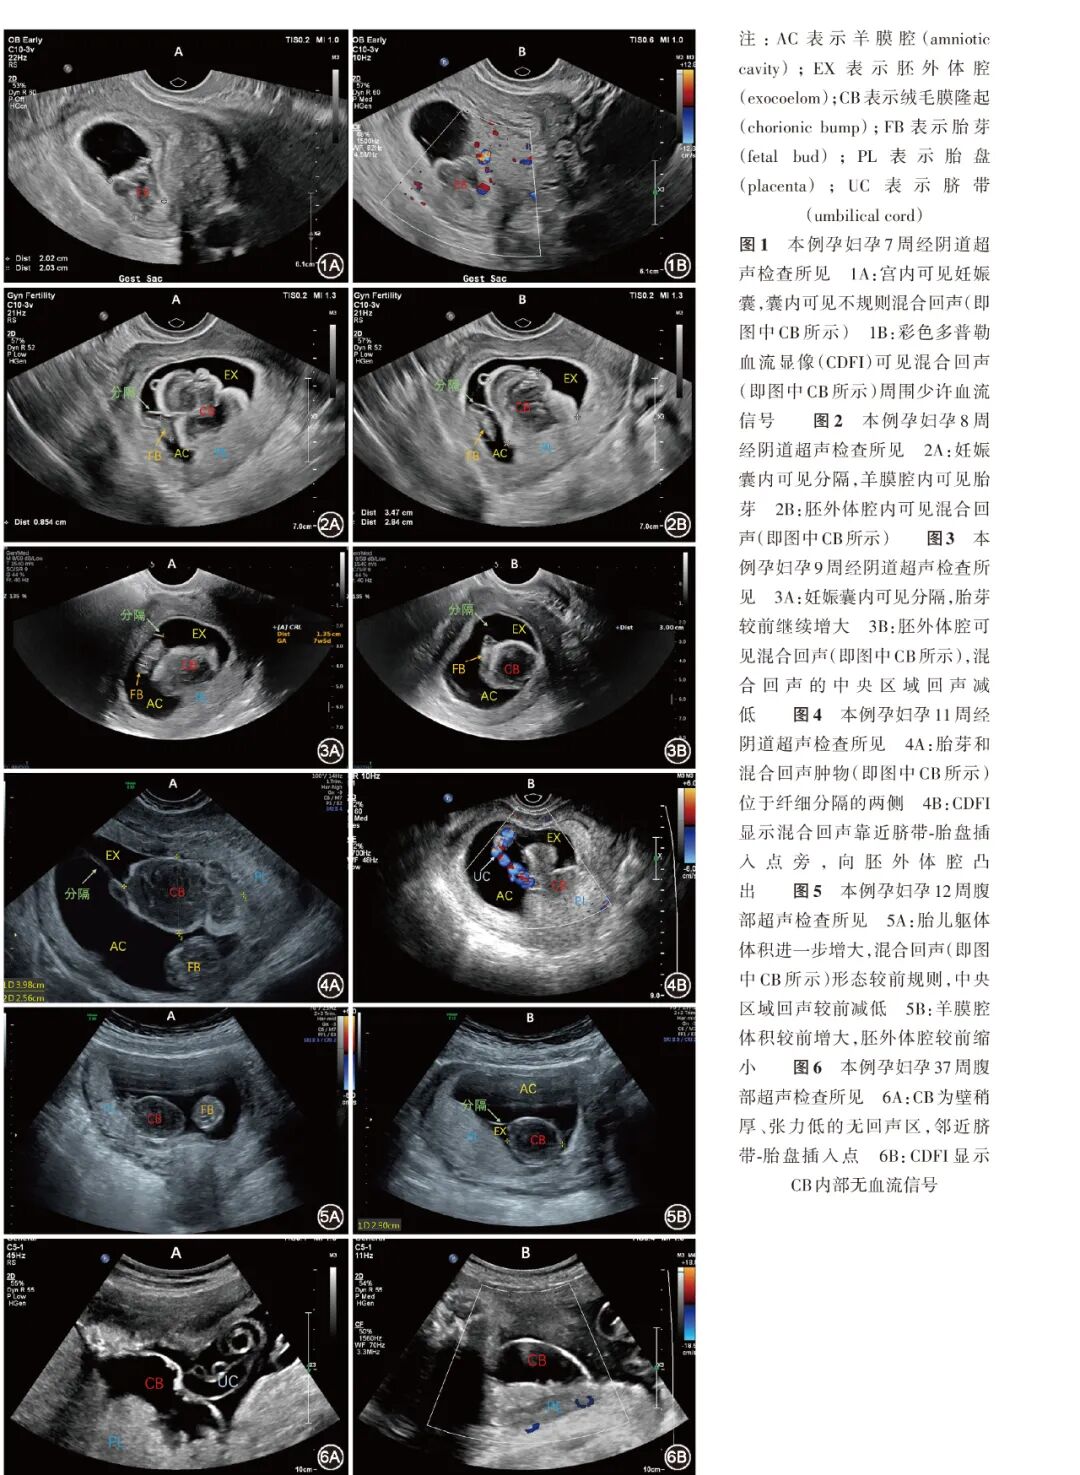

北京 100730;2中国医学科学院北京协和医学院 北京协和医院超声医学科,北京 100730通信作者:张一休, Email:yixiu241@163.com引用本文:张多多,黄姝伦,张一休. 体外受精-胚胎移植后妊娠并发绒毛膜隆起1例[J]. 中华妇产科杂志,2025,60(03):221-224.DOI:10.3760/cma.j.cn112141-20240918-00509早孕期绒毛膜隆起临床罕见,易误诊漏诊。本文报道1例辅助生殖治疗后妊娠的绒毛膜隆起孕妇,其于孕7周起超声检查发现宫腔内不规则混合回声,随访过程中该回声体积不断增大且人绒毛膜促性腺激素β亚单位水平最高时超过20万U/L,由于本例辅助生殖治疗的特殊临床情境和超声表现的不典型性造成了诊断的困难,一度误诊为妊娠滋养细胞疾病或复杂性双胎。最终在连续的超声检查随访中明确了混合回声的性质和来源,确诊为绒毛膜隆起。绒毛膜隆起作为少见的早孕期超声表现,本文对其诊断、鉴别诊断和持续随访超声影像学变化的过程进行了总结,并复习了相关文献,以期提高超声科及妇产科临床工作者对于绒毛膜隆起的认识。孕妇37岁,孕0产0,因不孕症且反复辅助生殖治疗未成功受孕就诊于本院,其配偶的年龄为37岁。2019年,孕妇32岁时因未避孕未孕3年、原因不明不孕,于外院行体外受精(in vitro fertilization,IVF),但反复种植失败,之后转诊本院继续辅助生殖治疗。于2024年5月6日人工周期解冻移植2个囊胚(Gardner评分分别为4BB、4BC),移植后第7天检验是否妊娠,血清人绒毛膜促性腺激素β亚单位(human chorionic gonadotropin-β subunit,β-hCG)为34 U/L,之后随访激素水平见 表1 。于孕7周时行经阴道超声检查,宫腔内可见妊娠囊,其内未见明确胎芽及胎心搏动;囊内可见不规则混合回声团,范围约2.0 cm×1.3 cm,回声团内部呈低回声,外部呈高回声,形态欠规则,与绒毛膜分界欠清;彩色多普勒血流显像(color Doppler flow imaging,CDFI)示上述混合回声的边缘近绒毛膜处可见少许点条状血流信号,内部未见明显血流信号。见 表1 ,图1 。孕妇无明显不适,每周密切随访。孕8周复查经阴道超声,妊娠囊增大,其内可见较薄分隔膜回声,分成两腔,其一腔(即羊膜腔)内可见胎芽(长约9 mm),可见胎心搏动;另一腔为胚外体腔,内可见卵黄囊及混合回声,混合回声体积较前增大,形态欠规则,边缘近绒毛膜处少许血流信号。见 图2 。孕9周时孕妇血β-hCG水平达20万余U/L,孕10周时血β-hCG水平下降为16.8万余U/L,同期复查超声显示胎芽增长,可见胎心;不规则混合回声体积较前略增大,混合回声中央区域的回声明显减低。见 图3 。孕妇无腹痛、阴道流血、心率快等不适表现,仅轻微恶心。孕11周血β-hCG水平下降为11.8万余U/L,复查经阴道超声示:宫内可见妊娠囊,其内的胎芽符合孕周;上述混合回声体积较前略减小,周围为高回声轮廓,中央为低回声,位于胎盘表面,靠近脐带-胎盘插入点旁,向胚外体腔内凸出;CDFI示无明显血流信号。见 图4 。超声诊断为绒毛膜隆起(chorionic bump,CB)。孕妇于孕12周完成颈部透明层(nuchal translucency)厚度超声检查,未见异常,CB进一步缩小,紧贴胎盘表面,胚外体腔进一步缩小,见 图5 。孕妇进入中孕期后无不适反应,黄体支持药物全部停用,规律产前检查。孕37周再次随访,孕期平顺,胎儿发育与孕周相符,暂无产兆,CB大小稳定,演变为内部完全呈无回声的低张力囊性结构,且无血流信号。见 图6 。

CB是妊娠早期较为罕见的超声表现,本文报道1例继发于IVF-胚胎移植的早孕期宫腔内大体积占位的孕妇,由于辅助生殖治疗的特殊临床情境和超声表现的不典型性,使得本例在病程早期的诊断和鉴别诊断较为困难,但最终诊断为CB。早孕期是胚胎发育和妊娠过程最为脆弱的时期,各种可能造成胚胎停止发育、流产的因素均为医患双方所关注。CB是妊娠早期较为罕见的超声表现,在2006年首次被描述为底蜕膜绒毛膜表面向妊娠囊内胚外体腔中的不规则凸起 [ 1 ] ,国外文献报道的发生率为0.15%~0.70% [ 1 , 2 ] ,我国较大样本量的两项研究报道的发生率为0.20%~0.42% [ 3 , 4 ] 。伴随着对早期胚胎结构及其超声表现认识的提高,近年来关于CB的报道逐渐增多,使之能被较系统地描述。本文报道的此例孕妇继发于IVF、早孕期超声表现为妊娠囊内大体积占位,但由于特殊的辅助生殖治疗背景和超声表现的不典型性,使得本例在早期未能被准确诊断,最终才诊断为CB。CB的病因、病理尚不完全明确,目前的主要观点认为,其本质是绒毛动脉出血引起的血肿 [ 1 ] ,即早期胎盘形成过程中,胎儿面绒毛膜板或绒毛间隙的动脉破裂,出血不能渗透出滋养层外,而向阻力较小的方向扩展,故血肿凸向妊娠囊内形成绒毛膜的隆起 [ 2 ] 。在超声检查中,CB常为单发的凸向妊娠囊内的不规则隆起结构,回声强度随出血时间和血肿的陈旧程度而多变,但最常见者为高回声、外层高回声但内层低回声或者等回声甚至无回声,其中高回声最为常见,约占51.72% [ 3 ] ;但多无彩色多普勒血流信号。本例在孕7~12周连续进行超声检查,可见病变内部为低回声、周边呈中高回声,随孕周进展内部回声逐渐减低,病变形态不规则,体积逐渐缩小;CDFI显示病变内无血流信号;上述特征均符合血肿的超声表现,也进一步支持了CB的病理本质系血肿性病变。本例的CB位于脐带-胎盘插入点旁,该处血管较粗大可能是造成局部绒毛膜出血且病变体积较大的主要原因。在随访过程中,部分CB可逐渐缩小至消失,这也符合血肿性疾病的表现 [ 1 ,5 ] 。也有文献报道通过磁共振成像(MRI)检查,可以见到CB中央区域在T 1加权成像上为低信号,而在T 1压脂序列成像上信号增强,也进一步印证了CB的病变结构为血肿[ 1 ] 。作为早孕期少见的超声表现,常俊杰等 [ 6 ] 报道了对于25例CB误诊率达到了100%,提示超声科及妇产科临床工作者需加强对这一超声表现及其鉴别诊断的认识。本例的特殊之处在于CB出现的孕周较早且体积较大,增长较迅速,与羊膜囊、胚外体腔的关系不易判断,造成了鉴别诊断困难。本例孕妇最早于孕7周超声检查发现妊娠囊内异常混合回声,体积增大明显;且β-hCG水平进行性增高,在孕9周达到20万余U/L;因此,临床医师曾考虑是否为妊娠滋养细胞疾病。妊娠滋养细胞疾病的特征为β-hCG水平异常且快速增高,完全性葡萄胎为宫腔内存在来自胎盘等滋养层结构的水泡样结构 [ 7 , 8 ] ,无胎芽及胎心搏动,与本例不符;部分性葡萄胎是因为异常受精造成的三倍体,胎盘局部水肿呈蜂窝囊状,但通常位于一个羊膜囊内,且部分性葡萄胎常于中孕期被诊断,β-hCG水平较少超过10万U/L [ 9 ] 。此外,由于本例孕妇移植了2个囊胚,临床诊疗过程中也曾高度怀疑双胎之一葡萄胎,双胎之一葡萄胎的β-hCG水平多高于10万U/L,由于正常胎儿的染色体正常,可获得40%左右的活产率,流产主要源于葡萄胎相关的并发症 [ 10 ] ;本例孕妇并不存在典型的水泡状结构,且该混合回声与胎儿位于同一妊娠囊内,不符合双胎之一葡萄胎的诊断;同时,本例孕妇β-hCG水平在孕10周后下降,并且不合并妊娠剧吐、甲状腺功能亢进、持续增大增多的卵巢囊肿等表现,更不符合双胎之一葡萄胎的诊断 [ 8 ] 。还有一类相关疾病为胎盘间叶发育不良,需要与CB鉴别,虽然胎盘间叶发育不良者β-hCG水平可轻度升高,但超声表现还是以胎盘滋养层内多发囊性病灶为主 [ 11 ] ,与本例并不相符。由于本例孕妇经阴道超声检查观察到妊娠囊内较薄的分隔膜,超声科及妇产科医师也曾考虑需要鉴别单绒毛膜双羊膜囊双胎的特殊并发症——动脉反向灌注序列征,其表现为独特的无心胎块结构,易与CB的表现混淆 [ 12 ] ;支持点是不规则且快速增大的宫腔内占位以及被分隔的妊娠囊、较高的β-hCG水平,但是,随后的超声检查随访中,观察到妊娠囊内的较薄分隔其实为正常胎儿的羊膜囊,混合回声周围无羊膜囊,且与卵黄囊同处于胚外体腔内,同时,CDFI并未显示进入“肿物”内部的脐带血流信号,且“肿物”中央的回声不断减低并且体积缩小,均否定了动脉反向灌注序列征的诊断。此外,早孕期另一类常见的出血性疾病为绒毛膜下血肿,其是绒毛膜与蜕膜之间出血形成血肿,绒毛膜与底蜕膜之间分离,多呈新月形、环形,多平行于妊娠囊,CDFI会显示其内无血流信号;而CB中绒毛膜与蜕膜之间无分离,无平行于妊娠囊方向的液性暗区 [ 13 ] ,所以CB的血肿不与宫腔相通,因此本例孕妇未出现阴道流血症状。CB与妊娠预后的关系尚存争议,大多数学者的观点认为,CB孕妇常无流产相关的腹痛、出血等症状体征,但流产率增加 [ 14 ] 。国内学者观察了87例CB孕妇,胚胎停止发育率为19.54%,而同期的正常对照组孕妇为5.08%,存在显著差异,但继续妊娠的CB孕妇未发现后续存在胎儿结构畸形 [ 3 ] 。在国外文献中也报道了自然妊娠后出现CB流产率约增加2倍,而在辅助生殖治疗后妊娠的CB孕妇中流产率增加至4~6倍 [ 1 , 15 ] 。CB的平均径线为10~20 mm,本例中CB病变最大时为4.9 cm×4.3 cm,较为罕见;但CB体积和位置与流产无明显关系,CB的数量与活产率负相关 [ 16 ] ,仅存在单一CB时活产率可达83% [ 14 ] 。另外,CB与胎儿染色体非整倍性无关 [ 17 ] ,而与妊娠期高血压疾病、胎儿生长受限及早产等可能与胎盘相关的疾病关系不明确 [ 15 ] 。研究结论存在不一致性主要源于CB临床发生率低,以及妇产科和超声科医师对CB认识不足发生了漏诊或误诊。综上,CB作为少见的早孕期超声表现,超声科及妇产科医师对其认识尚有局限性。作为妇产科临床医师,需要了解CB的存在,作为胎儿附属结构的病变,其在IVF与自然妊娠中的发生率和预后并无差别,处理以随访观察为主;还需注意孕妇血清β-hCG水平、是否存在阳性症状体征,做好与妊娠滋养细胞疾病、复杂性双胎或胎儿结构异常的鉴别诊断。超声科医师则需要加强对CB声像的认知,在超声检查时应尽量注意多个切面进行对比,适当结合多普勒血流信号辨认脐带血流位置;另还需加强对于早孕期妊娠物组织胚胎学结构的理解,明确病变所在的位置、来源;对于可疑双胎还要报告出绒毛膜性质,给临床更为精确的信息;此外,连续超声检查随访其变化,关注孕妇临床表现的进行性变化,以避免提供错误信息造成临床漏诊或误诊误治。